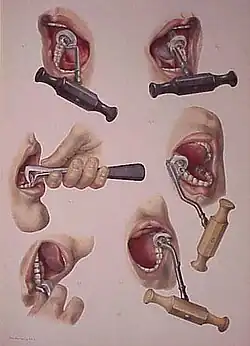

Removal of tooth

During extraction, multiple instruments are used to aid and ease the removal of the tooth whilst trying to minimally traumatise the tissues to allow for quicker healing. Extraction forceps are commonly used to remove teeth. Different shaped forceps are available depending on the type of tooth requiring removal, what side of the mouth (left or right) it is on and if it is an upper or lower tooth. The beaks of the forceps must grip onto the root of the tooth securely before pressure is applied along the long axis of the tooth towards the root.

Different movements of the forceps can be employed to remove teeth. Generally, while keeping downwards pressure attempts to move the tooth towards the cheek side (buccal) and then the opposite direction (palatal or lingual) are made to loosen the tooth from its socket.[2] For single, conical-rooted teeth such as the incisors, rotatory movements are also used.[2] A 'figure of eight' movement can be used to extract lower molars.[2]

Dental elevators can be used to aid removal of teeth. Various types are available that have different shapes. Their working ends are designed to engage into the space between the tooth and bone of the socket.[2] Rotatory movements are then made to dislodge the tooth from the socket.[2] Another similar looking but sharper instrument that can be used is a luxator; this instrument can be used gently and with great care to cut the ligament between the tooth and its boney socket (periodontal ligament).[2]